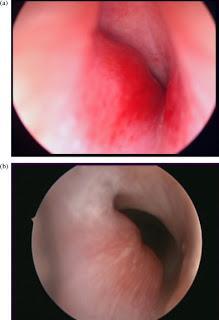

Hemangioma subglótico

Diagnóstico de los tumores vasculares

El 90% por la clínica y no tiene complicaciones ni se asocian a a otras patologías. Ahora, si existen dudas, o se quiere valorar la extensión o pueden existir malformaciones asociadas, puede usarse la ecografía doppler especialmente en hemangiomas lumbosacros, en niños con 5 ó más hemangiomas (eco hepática), en hemangiomas segmentarios faciales (eco cerebral). La resonancia magnética debe reservarse para casos concretos e individualizados (hemangiomas perineales extensos, hemangiomas de la vía aérea, atípicos, etc. Las pruebas endoscópicas, oftalmológicas etc se limitan a los casos raros en los que se complican o son de riesgo.